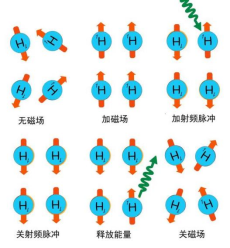

fMRI的基础是核磁共振成像(Magnetic Resonance Imaging,MRI)技术,因此我们先简要介绍一下后者的成像原理。当人体组织中的质子(由于人体大约70%以上是水,因此这里主要是指水分子中的质子,即氢原子核)被放置在强大的恒定磁场中时,这个磁场会使这些质子排列得更有序,并且大部分的质子都会沿着外部磁场的方向进行排列;此时,施加一系列的具有特定频率的射频(Radio Frequency,RF)脉冲,这些RF脉冲能够暂时扰乱质子的排列,使它们偏离原来与外部磁场所平行的方向;当RF脉冲被停止以后,质子就会逐渐返回到其初始的状态,也就是返回到重新与外部磁场所平行的状态,而在他们返回原始状态的过程中,质子会释放之前所吸收的能量,这个过程被称为弛豫(Relaxation),伴随着射频信号(即磁共振信号)的发射;计算机将这些磁共振信号收集起来,按强度转换为黑白灰阶,按位置组成二维或者三维的形态,最终组成核磁共振图像[1][2]。

图1 MRI原理示意图[2]